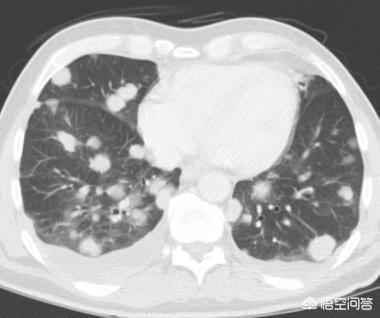

さらに1年2カ月後、2017年12月に3回目の検査を受けた。この結節は以前よりずっと大きくなっており、悪性の徴候が小葉状に広がり、内部が固くなっているのがわかる。これらの徴候から、基本的に肺がんと診断されたが、それでも患者は手術を受けなかった。

結節は腫瘤(3cm以上)に変化しており、この肺がんは教科書的なもので、基本的に肺がんを支持する悪性腫瘍の兆候をすべて備えている。不規則な境界、小葉、バリ、胸膜の引きつれの徴候。